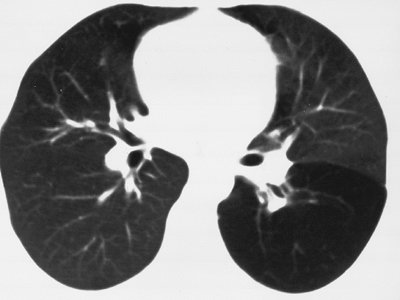

FIGURE 16-1. Congenital lobar emphysema. CT of a 30-year-old asymptomatic woman shows abnormal lucency and diminutive vasculature in the superior segment of the left lower lobe. There was no evidence of endobronchial lesion on CT or bronchoscopy, and the appearance of the left lower lobe was unchanged for 3 years on follow-up CT scans.